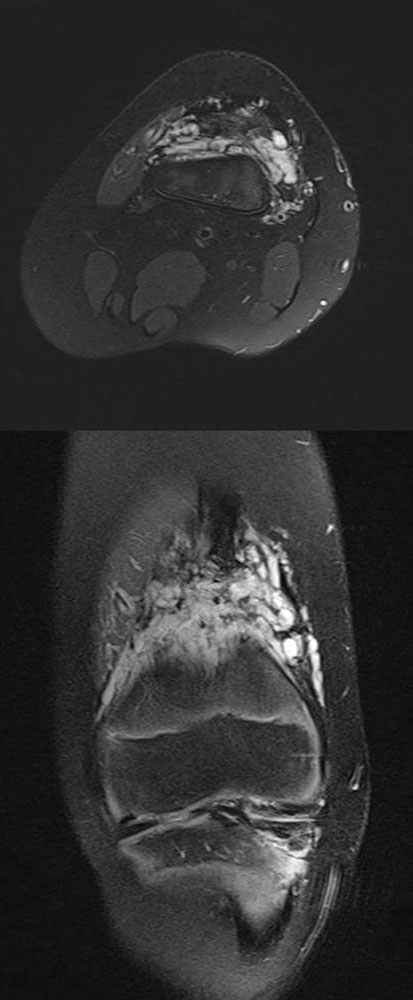

Sequelae occur in the affected body part when the development of neighboring structures such as bones, joints, muscles and tendons is disturbed by the expansion of the venous malformation. It can be assumed that both displacement, disturbed microcirculation (reduced oxygenation in the case of congestion) and restricted use play a role. In addition, segmental overgrowth and undergrowth syndromes may also occur, which according to recent findings are attributable to somatic mutations. These cases are characterized by increased asymmetry of the affected body parts.

The locally occurring musculoskeletal impairment is further aggravated by the asymmetry to the contralateral side. Growth is impaired, which can lead to misalignments of the facial skull, the spinal column and the extremities. Large venous malformations in the face can interfere with food intake, hearing, speech or visual acuity, so therapy should begin early to avoid psychomotor developmental delays. Extensive venous malformations on the forearm and hand muscles are painful and impair finger mobility. An infant’s sensory perception will be disturbed. Gripping, climbing and writing will be difficult or impossible to perform, depending on the dominant hand. These functional impairments must be recognized and addressed at an early stage. Large venous malformations on the leg can hinder walking and running, which can isolate the child from schoolmates and friends.